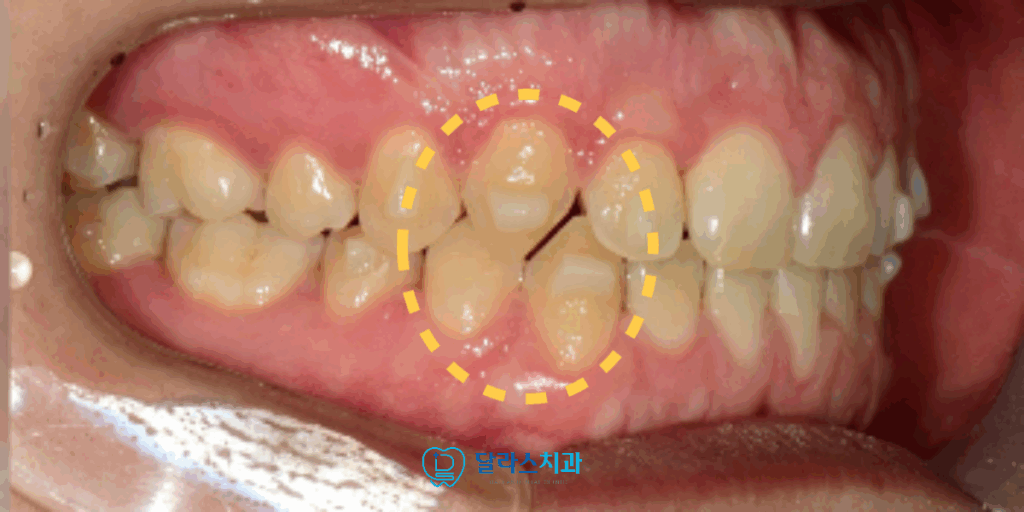

또 한 가지의 문제점은 송곳니가 너무 깊게 맞닿아있는 딥바이트로 인해서

정상적인 “Canine guidance” 가 이루어지지 못하고 있었습니다.

투명교정장치(Invisalign)를 활용해 교합평면을 재조정하고

송곳니의 위치를 뼈 속으로 함입시켜 재배열하였습니다.

이 과정을 진행한지 약 6개월만에 송곳니의 위치가 조정되어

교합이 열린 것을 확인할 수 있습니다.